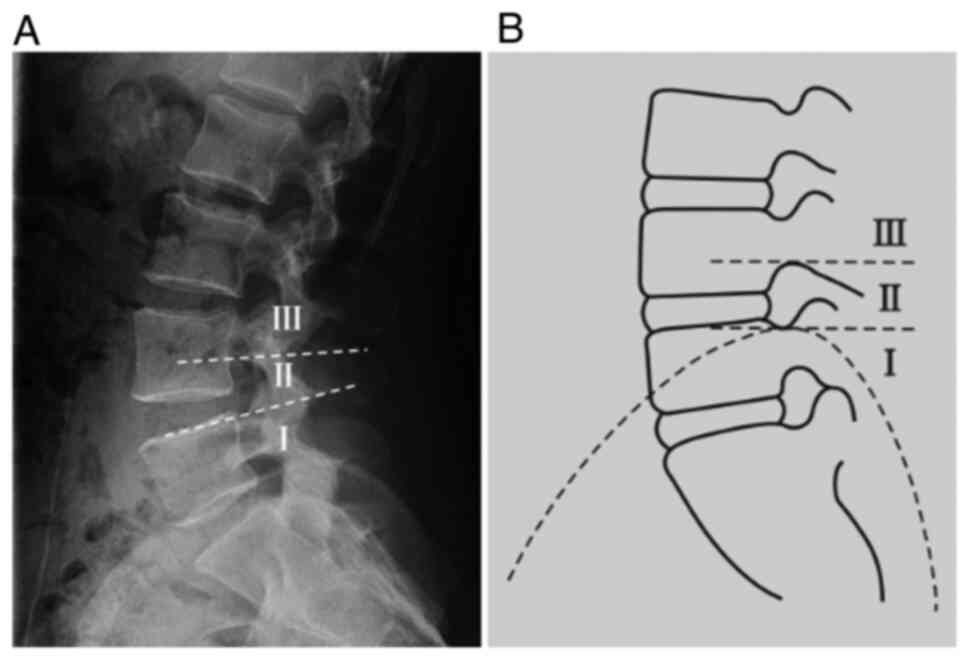

Inclusion criteria

The inclusion criteria were as follows: i) No lumbar instability at the L5-S1 segments was shown on the X-ray films taken in the lumbar dynamic position; ii) L5-S1 single-segment lumbar disc herniation; iii) no complications of spinal diseases, including lumbar spinal stenosis, spinal deformity and spinal tuberculosis and iv) ineffective conservative treatment. A total of 76 patients with lumbar disc herniation, including 46 male and 30 female patients aged 19-69 (mean age, 47.8±6.4) years, met the inclusion criteria and were treated with the THESSYS technique at the Second Affiliated Hospital and Third Affiliated Hospital of Xi'an Jiaotong University between January and December 2016. The study was approved by the Medical and Biological Ethics Committee of Xi'an Jiaotong University Health Science Center, and all participants signed the informed consent to the clinical study. These patients were divided into the following three groups according to the positional relation between the highest point of the iliac crest and the L4 and L5 pedicles in the lateral lumbar X-ray film: Group I, iliac crest height below the upper edge horizontal line of the L5 pedicle (n=42); group II, with iliac crest height between the lower edge horizontal line of the L4 pedicle and the upper edge horizontal line of the L5 pedicle (n=29) and group III, iliac crest height above the lower edge horizontal line of the L4 pedicle (n=5) (Fig. 1).

Figure 1

On the basis of the relationship between the highest point of the iliac crest and the L4 and L5 pedicles on the lumbar lateral radiograph, patients were divided into three groups. (A) Lateral radiography of the lumbar and (B) corresponding schematic illustration. The dotted line above represents the lower edge horizontal line of the L4 pedicle and the dotted line below demonstrates the upper edge horizontal line of the L5 pedicle. I represents iliac crest height below the upper edge horizontal line of the L5 pedicle. II indicates the iliac crest height between the lower edge horizontal line of the L4 pedicle and the upper edge horizontal line of the L5 pedicle. III represents the iliac crest height above the lower edge horizontal line of the L4 pedicle.